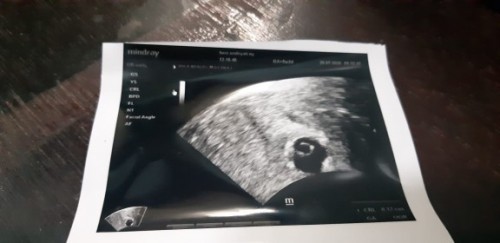

masih kantong itu blm ada janin

saya baru kantungnya doang bun

ini 4w bun